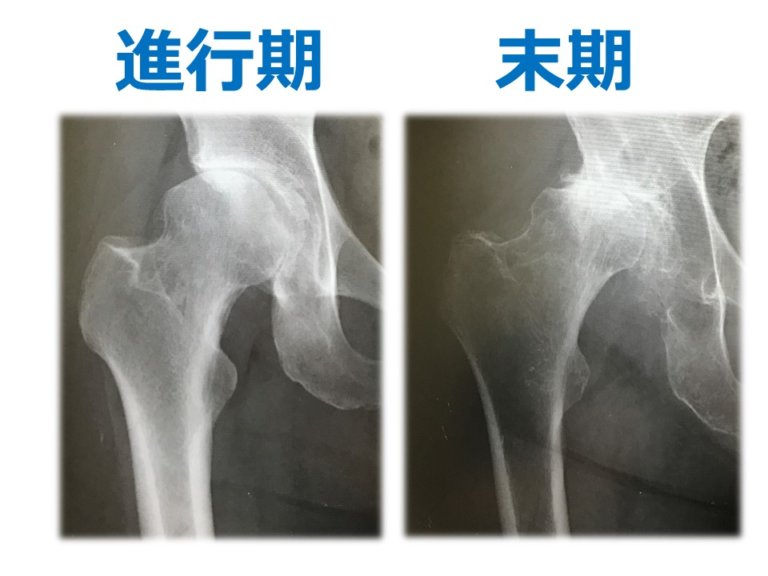

変形性関節症とも呼ばれる変形性関節症は、軟骨(2つの骨の間の摩擦を緩衝する機能を持つ組織)が老化し、強度が低下することで発生します。軟骨が損傷すると、骨が直接接触して動き始め、関節に重大な損傷を引き起こします。

進行性の病気であり、治療法はありません(軟骨が再生しない)ため、症状を軽減するには理学療法と鍼治療が効果的な治療法です。より具体的なケースでは、手術が要求される場合があります。